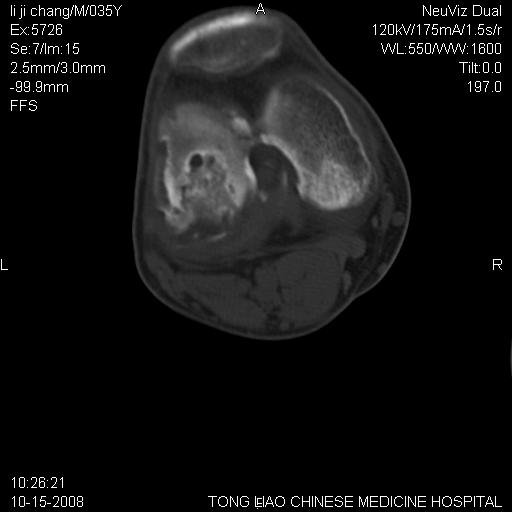

男,35岁,骨科诊断骨性关节炎。继往使用过激素,现股骨头坏死。膝关节病变,请会诊

一元论-----亦考虑为坏死

支持考虑无菌坏死

支持无菌坏死伴退行性骨关节病.

剥脱性骨软骨炎:是一种关节下软骨及软骨下骨缺血性坏死。

支持 无菌性坏死伴退行性骨关节病。